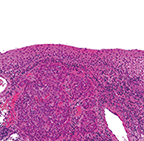

図❺ 病理組織画像

HE染色 原倍率×200 Scale bar=100μm。扁平上皮類似の異型細胞集団が粘膜上皮下に浸潤増殖している